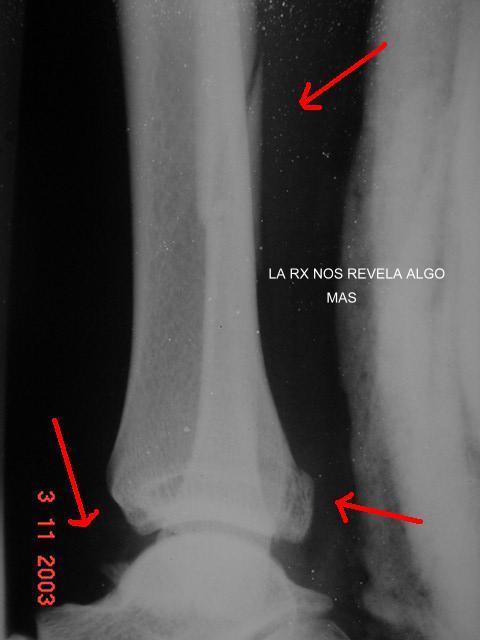

fRACTURA MULTIPLE DE TOBILLO

Las tres Rx son del mismo paciente. UNA RADIOGRAFÍA de pierna que cataloga al paciente como fractura del peroné solamente. La clínica se impone. Las otras radiografías confirman a la clínica.